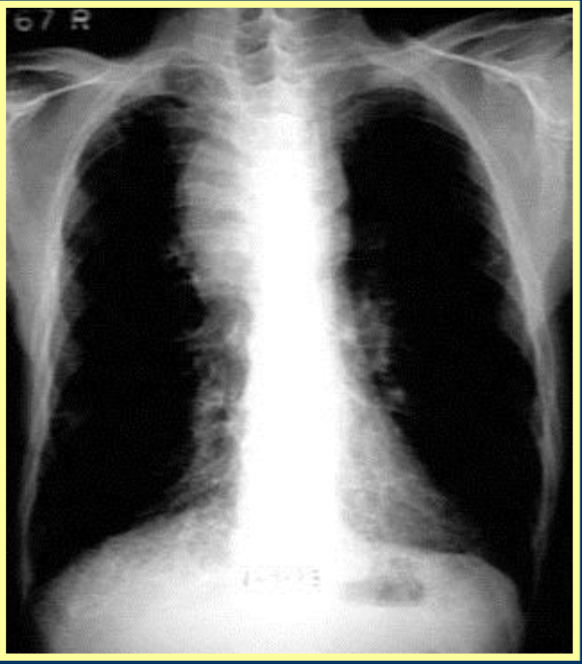

Patient initially presents with flu-like Sx including malaise, cough, myalgia, hypoxia, dyspnea, but no rhinitis

CXR shows mediastinal widening and lymph nodes appear swollen

Likely diagnosis?

Pulmonary or inhaled anthrax